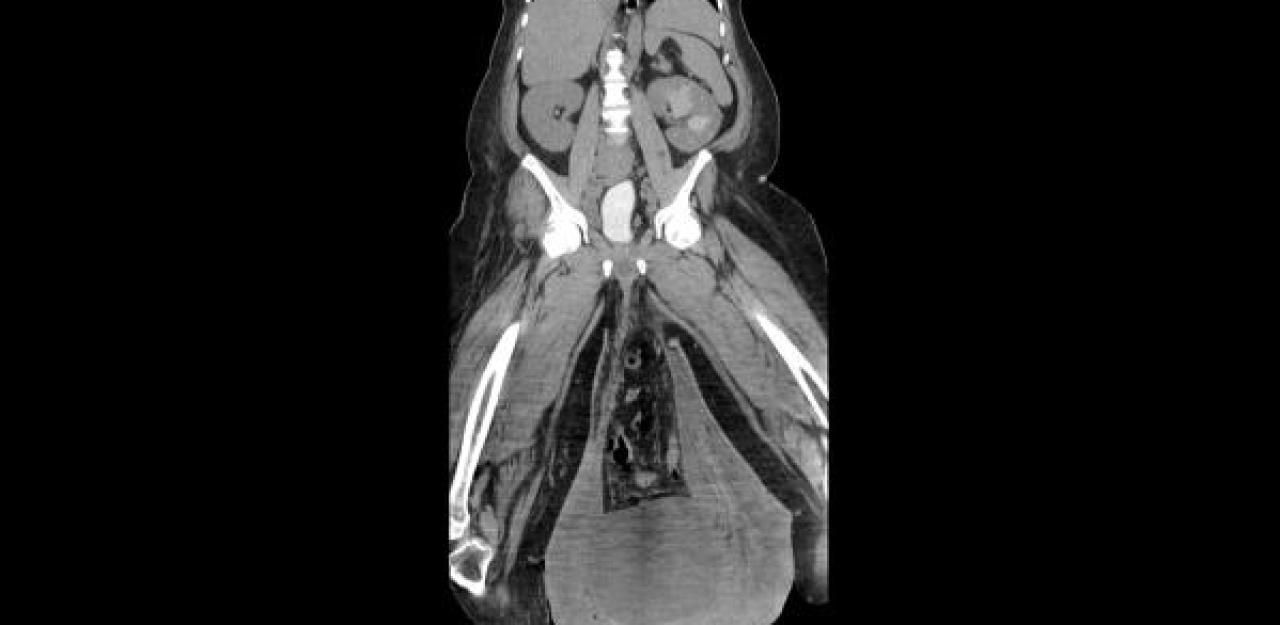

Im Krankenhaus diagnostizierten die Mediziner ein sogenanntes "massives Skrotalödem (Schwellung des Hodensacks) mit Verschiebung über das Knieniveau hinaus" (siehe Bildstrecke). Auch die Haut sei verdickt, außerdem seien zwei große Wunden zu sehen, aus denen eine "übelriechende, eitrige Flüssigkeit" ausgetreten sei, heißt es im Fachjournal "Urology Case Reports".

Die Ursache des Leidens machten die Ärzte schließlich auf Röntgenbildern von Bauchraum und Becken des Patienten aus: ein seit Jahrzehnten nicht behandelter Leistenbruch. Seither wölbte sich ein Teil seines Darms durch die vordere Bauchwand, wodurch es in der Folge zu einem Lymphödem des Hodensacks kam.